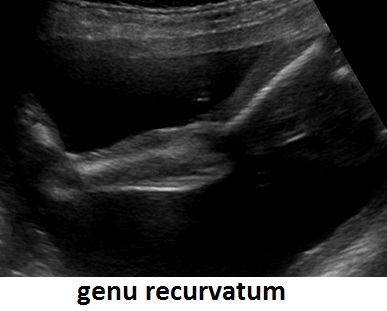

Bisogna valutare anche le alterazioni dell'asse tra segmento mesomelico e quello acromelico; tra queste rara è l'alterazione dell'asse tra avambraccio e mano (mano torta) mentre è frequente l'alterazione dell'asse tra gamba e piede ( Piede Torto ) che può essere espressione di varie patologie quali: spina bifida, idrocefalia, cromosomopatia (es. trisomia 18,.....), oligoidramnios, etc…..